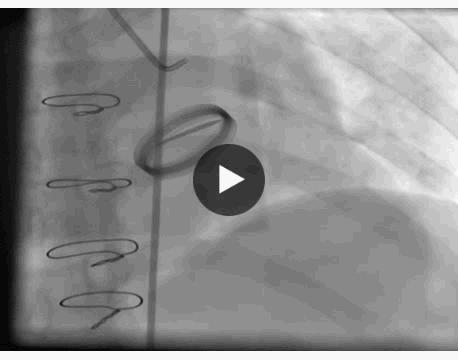

冠脉造影显示:左主干未见明显异常,前降支近中段动脉硬化,未见明显狭窄及血栓,远端血流TIMI 3级,回旋支全程可见散在斑块,近段局限性狭窄约50%,远段血栓影消失,远端前向血流TIMI 3级。

右冠脉动脉硬化,近中段可见多处局限性斑块病变轻度狭窄,远端血流TIMI 3级。 结论:符合冠心病、急性心肌梗死改变,目前回旋支远段血栓自溶,未见明显狭窄病变,暂不予以支架植入。

主要造影结果

月经期结束后复查冠脉造影显示,回旋支远段血栓影消失,远端前向血流TIMI 3级。

回旋支远段血栓自溶,考虑为抗凝、抗血小板作用及患者月经期凝血状态、雌激素水平改变共同影响。处于月经期女性发生急性心肌梗死,若病情平稳应如何处理,目前指南并没有明确推荐。